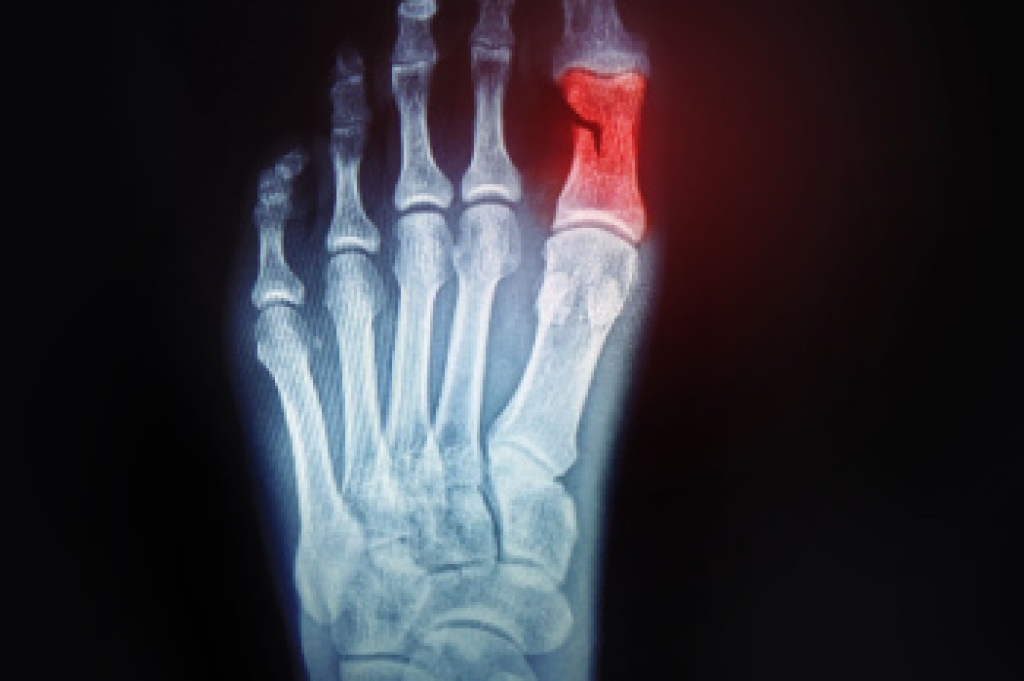

Broken toes, while often underestimated, can significantly impact daily activities and mobility. Common causes of broken toes include traumatic injuries such as stubbing or dropping heavy objects on the foot, as well as sports-related incidents and accidents. Symptoms of a broken toe typically include pain, swelling, bruising, and difficulty bearing weight on the affected foot. In severe cases, the toe may appear visibly misaligned or deformed, and there may be an audible popping or cracking sound at the time of injury. Additionally, individuals may experience numbness or tingling sensations in the affected toe. The appearance of a broken toe can vary depending on the severity of the injury, with some cases showing obvious signs of displacement or angulation, while others may have subtle swelling and discoloration. If you have fractured your toe, it is suggested that you consult a podiatrist who can perform an accurate diagnosis, and offer the treatment method that is best for you.

Although most people try to avoid foot trauma such as banging, stubbing, or dropping heavy objects on their feet, the unfortunate fact is that it is a common occurrence. Given the fact that toes are positioned in front of the feet, they typically sustain the brunt of such trauma. When trauma occurs to a toe, the result can be a painful break (fracture).

Severe toe fractures may be treated with a splint, cast, and in some cases, minor surgery. Due to its position and the pressure it endures with daily activity, future complications can occur if the big toe is not properly treated.